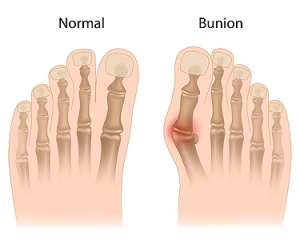

Various Types of Bunions

What Is a Bunion?

Bunions are painful bony bumps that usually develop on the inside of the foot at the joint of the big toe. As the deformity increases over time, it may become painful to walk and wear shoes. Women are more likely to exacerbate existing bunions since they often wear tight, narrow shoes that shift their toes together. Bunion pain can be relieved by wearing wider shoes with enough room for the toes.

Bunions

A bunion is an enlargement of the base joint of the toe that connects to the foot, often formed from a bony growth or a patch of swollen tissues. It is caused by the inward shifting of the bones in the big toe, toward the other toes of the foot. This shift can cause a serious amount of pain and discomfort. The area around the big toe can become inflamed, red, and painful.

Bunions are most commonly formed in people who are already genetically predisposed to them or other kinds of bone displacements. Existing bunions can be worsened by wearing improperly fitting shoes. Trying to cram your feet into high heels or running or walking in a way that causes too much stress on the feet can exacerbate bunion development. High heels not only push the big toe inward, but shift one's body weight and center of gravity towards the edge of the feet and toes, expediting bone displacement.

A podiatrist knowledgeable in foot structure and biomechanics will be able to quickly diagnose bunions. Bunions must be distinguished from gout or arthritic conditions, so blood tests may be necessary. The podiatrist may order a radiological exam to provide an image of the bone structure. If the x-ray demonstrates an enlargement of the joint near the base of the toe and a shifting toward the smaller toes, this is indicative of a bunion.